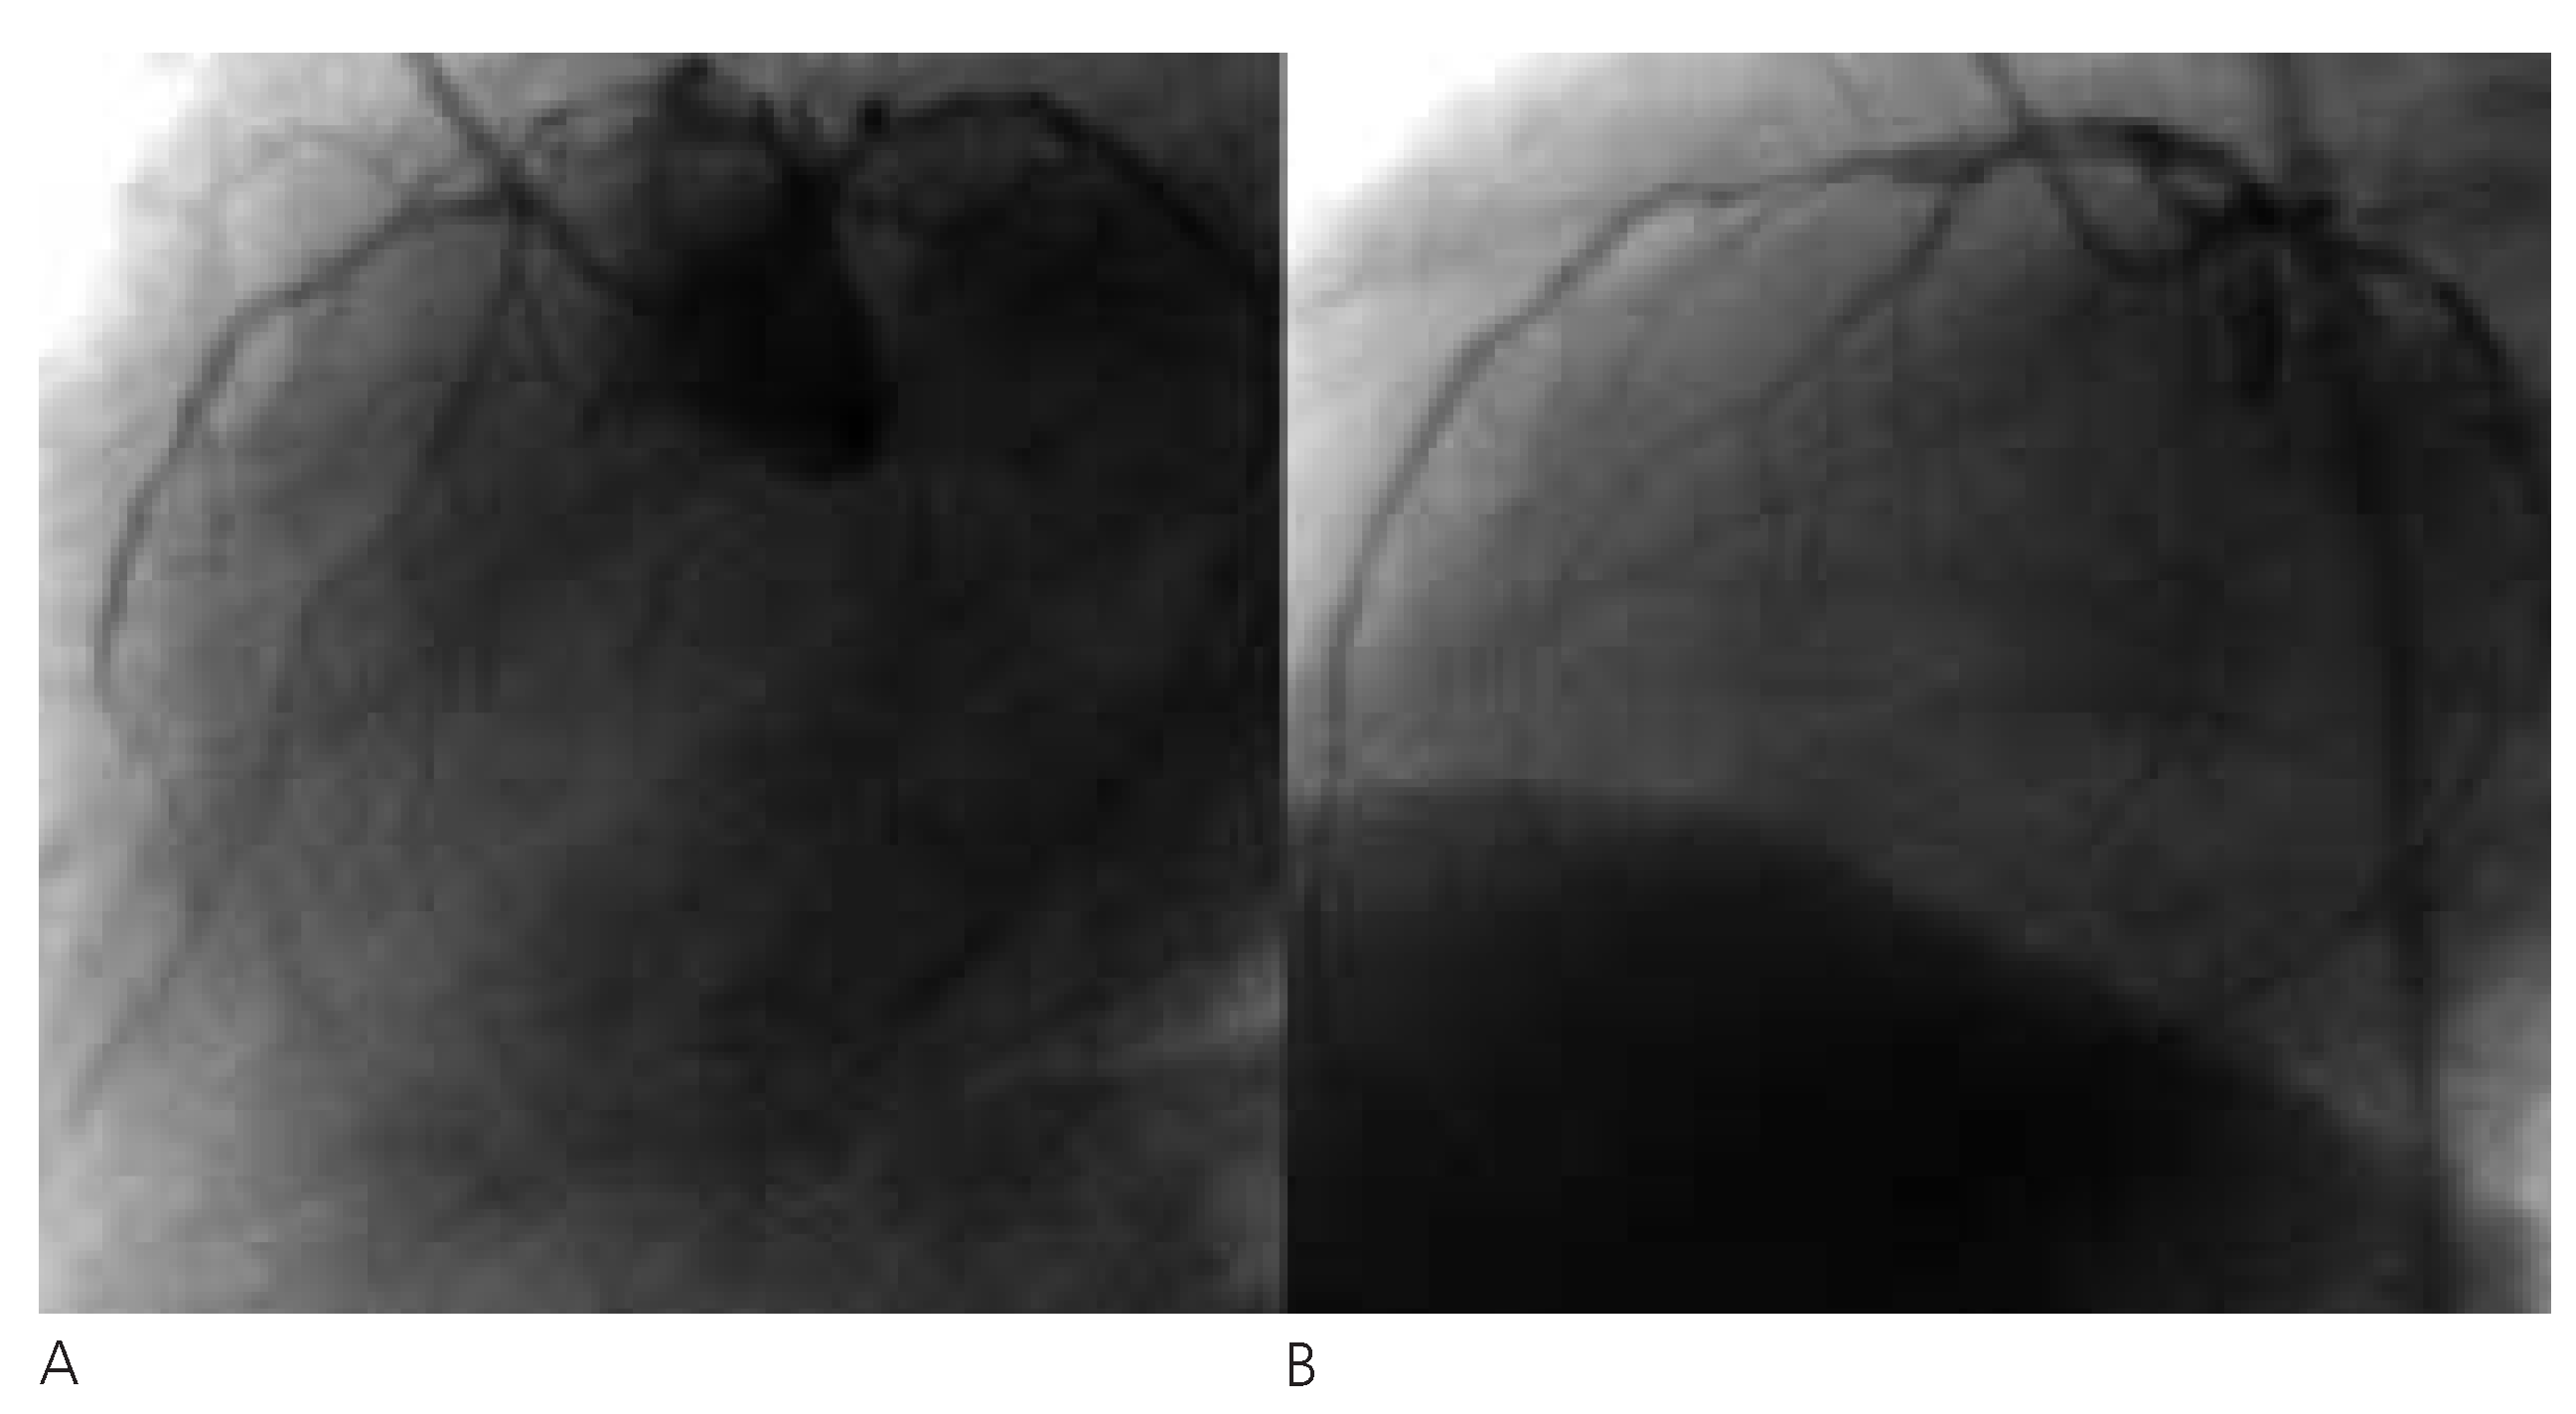

Abbildung 4. Das BiPAP-Gerät gewährleistet während des ganzen Atemzyklus einen kontinuierlichen positiven Druck in den Atemwegen. Im Gerät befindet sich ein Druckregelventil, welches Veränderungen vom eingestellten Druck registriert und den Fluss (V) im Schlauchsystem so anpasst, dass der eingestellte Druck in Inund Expiration stabil bleibt. Das heisst, dass bei Inspiration durch den Patienten (P) der Flow erhöht werden muss. Unter Helmbeatmung erfolgt die Exspiration durch ein PEEP-Ventil (PEEP), das einen zu raschen Druckabfall verhindert.

Wie können wir die Revaskularisationsrate bei Patienten mit akutem Koronarsyndrom und Lungenödem erhöhen? Die Therapie des akuten Lungenödems mittels CPAP wurde schon 1938 beschrieben und wird seit Jahren bei Patienten im kardiogenen Lungenödem angewendet [6]. In zwei randomisierten Studien mit Patienten im kardiogenen Lungenödem konnte ein Benefit bezüglich Oxygenierung, Atemfrequenz, Intubationsrate und Hospitalisationsdauer für die mit CPAP behandelten Patienten gegenüber der Gruppe mit konventioneller Sauerstofftherapie gezeigt werden [7, 8]. Ein wichtiges Problem bei CPAP und nichtinvasiver Beatmung sind die dafür notwendigen eng sitzenden Beatmungsmasken, die Angstreaktionen auslösen können und wegen Druckstellen und Lecks nicht unproblematisch in der Anwendung sind. Die neuen Beatmungs-«Helme» (Abb. 2) erlauben eine unkomplizierte und für die meisten Patienten sehr gut verträgliche Anwendung eines kontinuierlichen positiven Luftwegsdruckes (CPAP). Die Funktionsweise einer CPAP-Beatmung ist im Schema dargestellt. Der intrathorakale Überdruck reduziert das beim Lungenödem erhöhte Lungenwasser, verbessert die Oxygenierung und reduziert die massiv erhöhte Atemarbeit, was eine wesentliche Kreislaufentlastung darstellt. Es entsteht somit ein Zeitfenster, in dem eine Koronarintervention früh und unter Vermeidung einer Intubation durchgeführt werden kann. Da bei CPAP-Beatmung der Patient im Gegensatz zum frisch Intubierten selber atmet, kann auf den schweren Intensivstation-Ventilator verzichtet werden, der den Patiententransport wesentlich kompliziert. Stattdessen verwenden wir bevorzugt einen kleinen Transport-Ventilator oder ein BiPAP-Gerät, wie es auch zur Heimventilation verwendet wird und welches innert Minuten auch im Katheterlabor verfügbar ist. Natürlich kann bei Versagen dieser Therapie jederzeit auf die Intubation und maschinelle Beatmung umgestiegen werden, was den Sauerstoffverbrauch und damit die kardiale Belastung zwar weiter senken kann, aber in der Regel mit einem erheblichen Zeitverlust und nicht selten mit einer deutlichen, sedationsbedingten Kreislaufinstabilität erkauft werden muss.